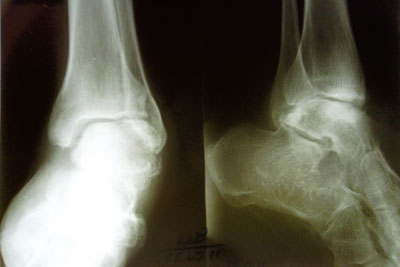

Рентген до операцииРентген до ОП